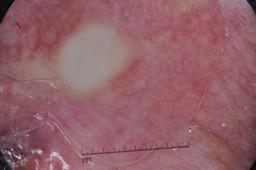

ISIC-DICM-17K (ISIC Dermoscopic Images and Clinical Metadata 17K) is a curated and balanced dataset derived from the International Skin Imaging Collaboration (ISIC) Archive Gallery. It comprises 17,060 dermoscopic images and clinical metadata (8,530 melanoma and 8,530 non-melanoma classes).

For more details, please follow the project’s GitHub repository: https://github.com/mmu-dermatology-research/isic-dicm-17k

This dataset was used in this study and benchmark to explore the effectiveness of multimodal learning for skin lesion classification:

S. Ahammed, X. Cui, W. Lu and M. H. Yap, "Skin Lesion Classification using Dermoscopic Images and Clinical Metadata: Insights from Multimodal Models," 2025 IEEE/CVF Conference on Computer Vision and Pattern Recognition Workshops (CVPRW), Nashville, TN, USA, 2025, pp. 222-230, DOI: 10.1109/CVPRW67362.2025.00027